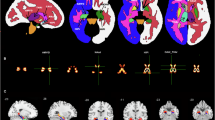

The percentages of naïve T cell subpopulations, including CD4 + CD45RA + , CD8 + CD45RA + , CD4 + CD45RA + CD95 + , and CD8 + CD45RA + CD95 + T cells, were lower in the SCZ group than in the HCs; in contrast, the percentages of memory T cell subpopulations, including CD4 + CD45RO + , CD4 + CD95 + , CD4 + CD45RO + CD95 + , CD8 + CD45RO + , and CD8 + CD45RO + CD95 + T cell subsets, were higher in the SCZ group than in the HCs (Table 3; Fig. 1). The level of IL-1β in naïve CD8 + CD45RA + CD95+ and memory CD8 + CD45RO + CD95 + T cell subsets, as well as the level of IL-6, TNF-α derived from CD8 + CD45RO + CD95 + T cell subpopulations, were higher in the SCZ group than in the HCs. However, the levels of other cytokines did not differ significantly between the groups (Table 4).

Subcortical volume and cortical thickness

Regarding subcortical volumes, the volumes of the ventricles, left and right CPs were larger in the SCZ group than in the HC group. The average thicknesses of the left and right cerebral hemisphere were thinner in the SCZ group than in the HC group (Table 5). Although the differences were not significant between the groups, comparisons of left and right IPL thickness were presented in Table 5, as IPL_R was the mediator in the following mediation and moderated mediation models. Other subcortical volumes and cortical thickness measures that demonstrated statistically significant group differences showed non-significant correlations with immunosenescence markers or MCCB scores or failed to mediate the effects of immune dysregulation on cognitive deficits.

Immunosenescence markers, structural imaging data, and cognitive manifestations

In the preliminary analyses, we systematically examined correlations among all cognitive metrics (seven subscale scores and one total score of MCCB), immunosenescence markers (T cell subpopulation percentages and intracellular cytokine levels), and structural imaging data (subcortical volumes and cortical thicknesses). The results demonstrated that intracellular IL-1β level (derived from CD8 + CD45RA + CD95 + T cells) exhibited significant pairwise correlations with working memory and cortical thickness in the bilateral IPL (IPL_L and IPL_R) and bilateral supramarginal gyri (SMG_L and SMG_R) in the SCZ group. However, these correlations were not significant in the HC group. The sensitivity analyses demonstrated that the findings remained statistically significant when Spearman correlation analyses were employed (Supplementary Materials). In subsequent mediation analyses, with the level of IL-1β (derived from CD8 + CD45RA + CD95 + T cell subpopulations) as the independent variable, working memory as the dependent variable, IPL_L, IPL_R, SMG_L and SMG_R thickness as the mediator respectively, with sex, age, ICV and hCPR level as covariates, only the IPL_R thickness emerged as a statistically significant mediator. The pairwise correlations between the level of IL-1β, IPL_R thickness, and working memory were shown in Fig. 2A–C, the corresponding mediation model was shown in Fig. 3A, in which the indirect and total effects were significant, whereas the direct effect was not. The mediation models with IPL_L, SMG_L, and SMG_R thickness as the mediator, respectively, were detailed in the supplementary materials. Further, in the moderated mediation analysis, the right CP volume was a moderator in the relationship between the above IL-1β level and the IPL_R thickness (Fig. 3B). Specifically, the IPL_R thickness mediated the association between the above IL-1β level and working memory at low (16th percentile) and moderate (50th percentile) levels of CP_R volume, but not at high level of CP_R volume (84th percentile) (Fig. 3B), which suggested that the volume of CP_R negatively moderated the positive association between the IL-1β level and the IPL_R thickness (Fig. 3C). The mediating and moderated mediating effects were not significant in the HCs.

A–C The level of IL-1β derived from CD8 + CD45RA + CD95 + T cell subsets was positively correlated with the IPL_R thickness and working memory, and the IPL_R thickness was also positively correlated with working memory in patients with SCZ, but those correlations were not significant in HCs. IPL inferior parietal lobule, SCZ schizophrenia, HC healthy control.

A Mediation analysis: X: The level of IL-1β derived from CD8 + CD45RA + CD95 + T cells; Mediator: IPL_R thickness; Y: Working memory. B Moderated mediation analysis: X represents the level of IL-1β derived from CD8 + CD45RA + CD95 + T cells; Mediator: IPL_R thickness; moderator: CP_R volume; Y: Working memory. C Moderation of effect of the above IL-1β level on IPL_R thickness by CP_R volume. IPL inferior parietal lobule, CP choroid plexus.